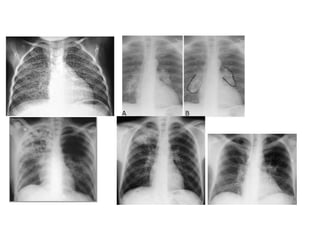

Radiological diagnosis

Chest X-ray

CXR remains an important tool for diagnosis of PTB in children who are sputum smear

negative or who cannot produce sputum

The following abnormalities on CXR are suggestive of Tb :-

• Enlarged hilar lymph nodes and opacification in the lung tissue.

• Miliary mottling in lung tissue

• Cavitation (tends to occur in older children)

• Pleural or pericardial effusion – though seen on CXR – are forms of extra

pulmonary TB that tend to occur in older children

• The finding of marked abnormality on CXR in a child with no signs of respiratory

distress (no fast breathing or chest indrawing) is supportive of TB

Primary Tuberculosis on CXR

1.GangliopulmonaryTB ( Characterized by the presence of

mediastinal and/ or hilar lymphadenopathy and

parenchymal abnormalities, the Ghonfocus

2.TuberculousPleuritis

3.MiliaryTB

4.Tracheobronchial TB

Radiological diagnosis Chest X-ray CXRremains an important tool for diagnosis of PTB in children who are sputum smear negative or who cannot produce sputum The following abnormalities on CXR are suggestive of Tb :- • Enlarged hilar lymph nodes and opacification in the lung tissue. • Miliary mottling in lung tissue • Cavitation (tends to occur in older children) • Pleural or pericardial effusion – though seen on CXR – are forms of extra pulmonary TB that tend to occur in older children • The finding of marked abnormality on CXR in a child with no signs of respiratory distress (no fast breathing or chest indrawing) is supportive of TB

Primary Tuberculosis onCXR 1.GangliopulmonaryTB ( Characterized by the presence of mediastinal and/ or hilar lymphadenopathy and parenchymal abnormalities, the Ghonfocus 2.TuberculousPleuritis 3.MiliaryTB 4.Tracheobronchial TB